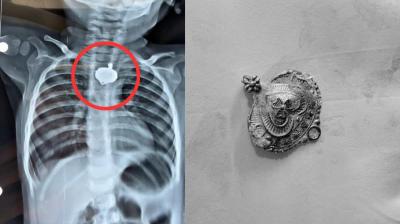

बड़वानी में 9 माह के बच्चे की आहार नली में फंसा मंगलसूत्र, डेढ़ महीने बाद एक्स-रे से खुलासा

24 Nov, 2025 08:30 AM IST | DAILYNEWSMPCG.COM

बड़वानी: रविवार को जिला अस्पताल में एक बेहद संवेदनशील और हैरान करने वाला मामला सामने आया. जब 9 माह के एक बच्चे के गले में मंगलसूत्र फंसा हुआ देखा गया. घटना...